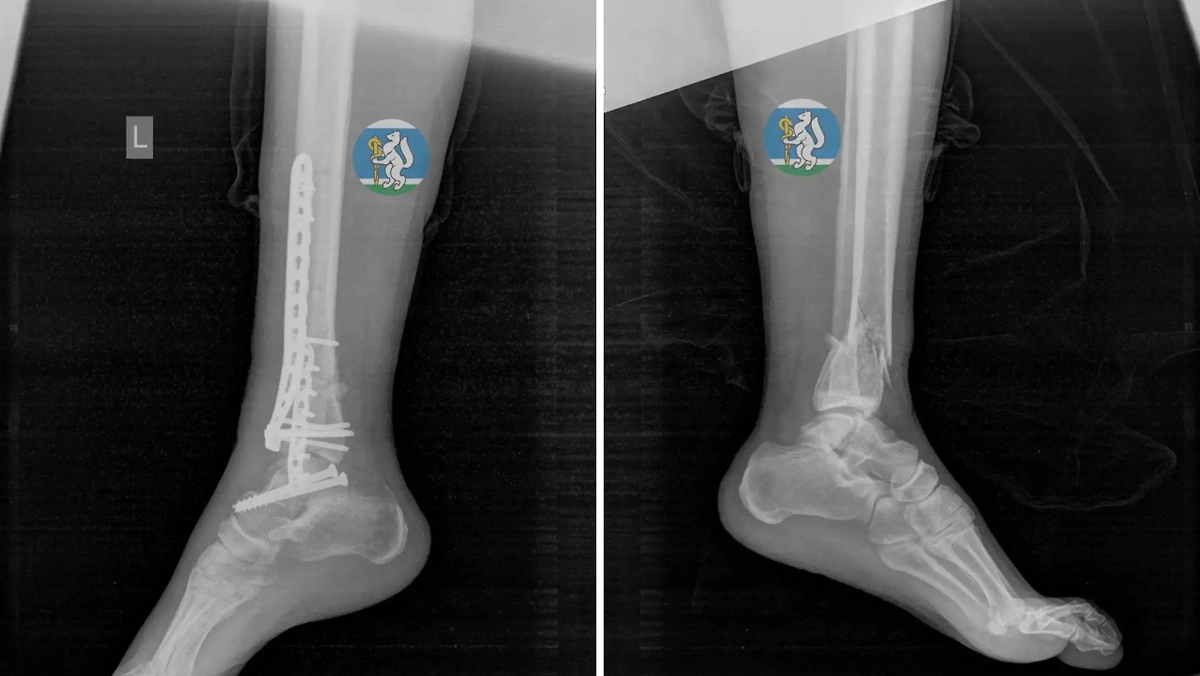

У пациентки выявили тяжёлые повреждения: травму головы, повреждение шейного отдела позвоночника, множественные переломы таза, а также повреждения грудной клетки с поражением лёгких и серьёзные переломы ноги. Специалисты отметили, что подобные травмы часто заканчиваются летальным исходом ещё до прибытия в медучреждение.

После проведения операции женщину перевели в реанимацию, где она находилась на аппарате искусственной вентиляции лёгких до стабилизации состояния. Позже её перевели в травматологическое отделение, где провели дополнительное хирургическое вмешательство. Врачи выполнили коррекцию фиксаторов и восстановление костей. В настоящее время пациентка выписана и проходит курс реабилитации.